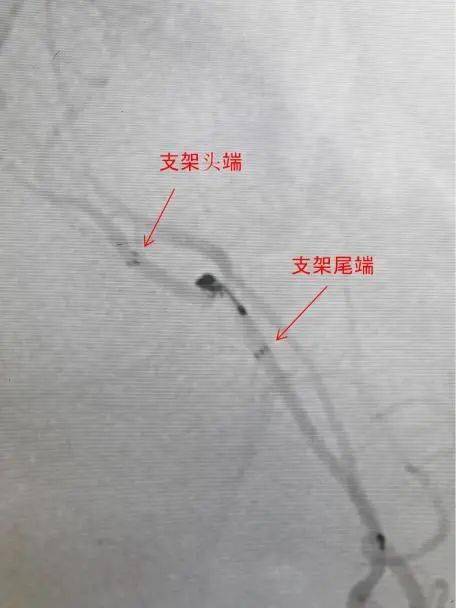

汇报1例:经右挠动脉入路,atlas开环支架"神龙摆尾"技术 - 抖音

经scepter c球囊导管释放atlas支架球囊辅助后释放支架atlas向左滑动